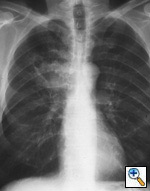

Fig. 45a: Posterior-anterior radiograph shows a right upper lobe mass, contiguous with the mediastinum. The appearance is consistent with a T3 bronchogenic carcinoma.